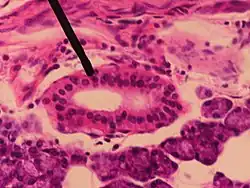

-

Section of submaxillary gland of kitten. Duct semidiagrammatic. X 200. -

Section of portion of mamma.